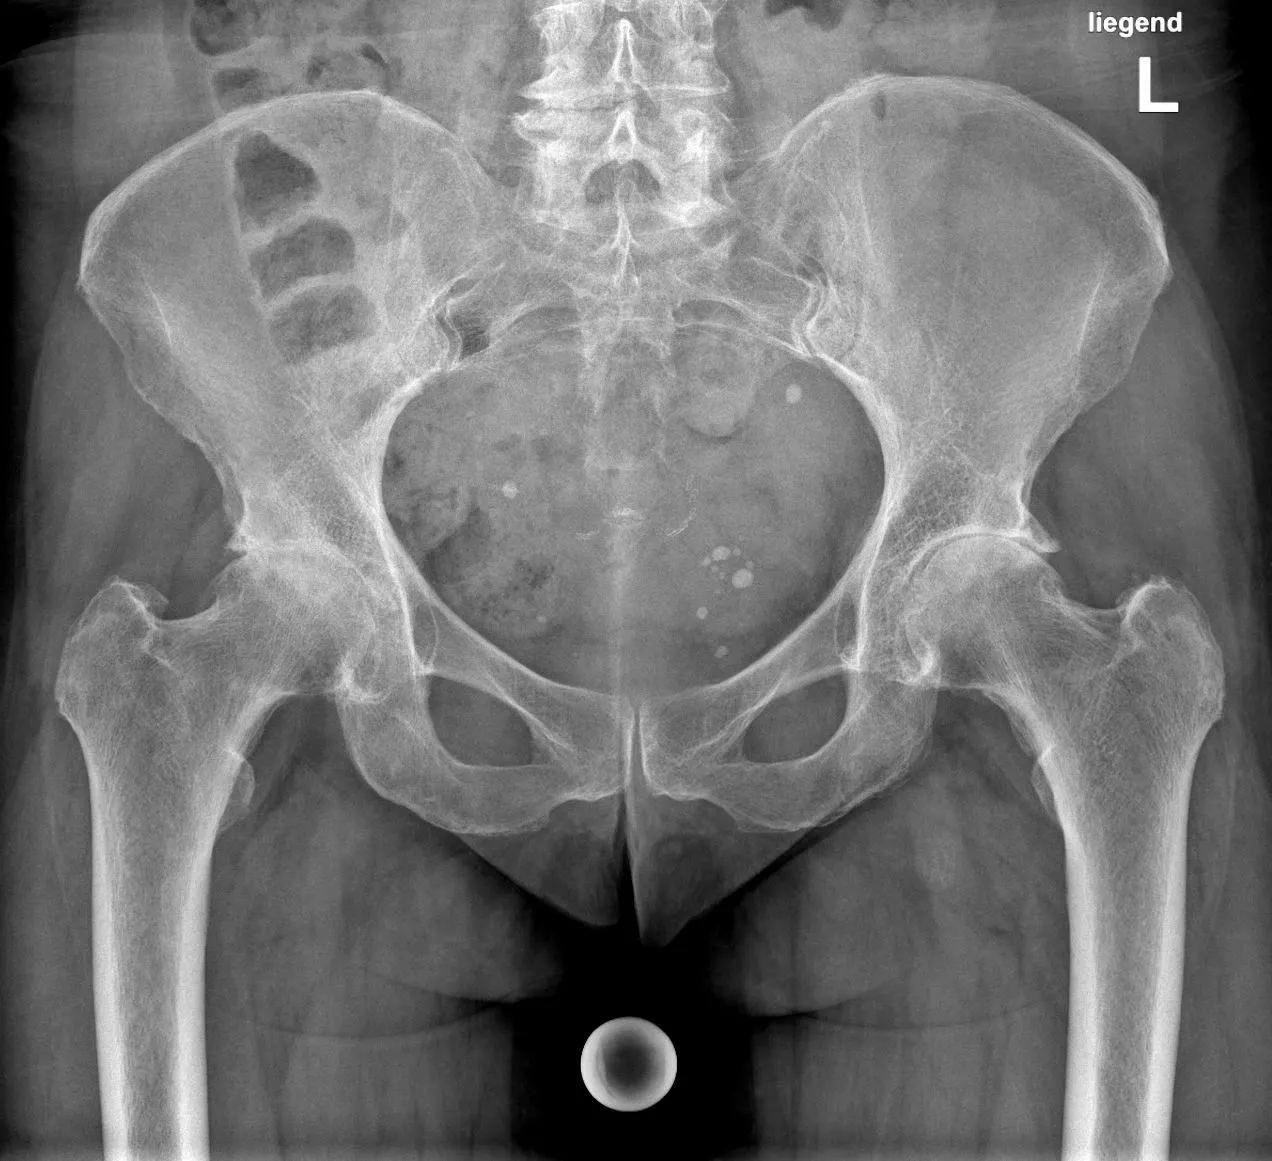

Röntgenbild einer Coxarthrose präoperativ